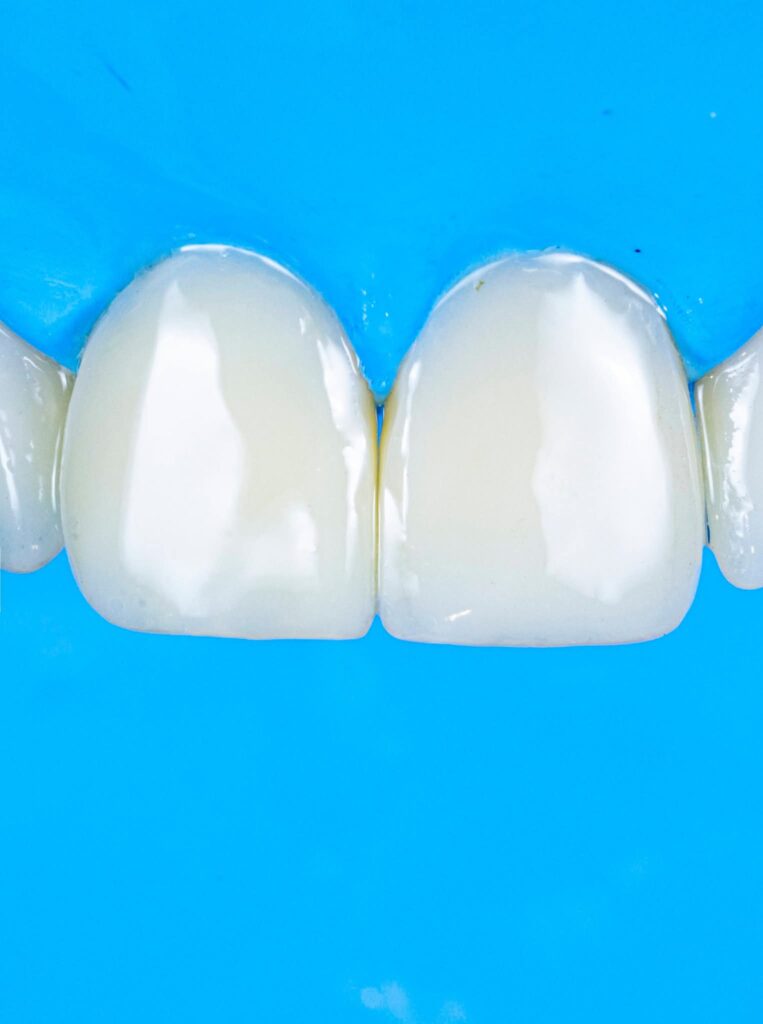

Proportionality relates to the width-to-length ratio and the relationship between anterior teeth. The ideal width/length ratio for central incisors is approximately 75–80%, and the apparent width proportion between anterior teeth often follows the golden proportion (~62%), although modern aesthetic dentistry prefers the concept of Recurring Esthetic Dental (RED) proportion for more natural results.

3. Surface texture and light reflection

4. Incisal translucency and halo effects